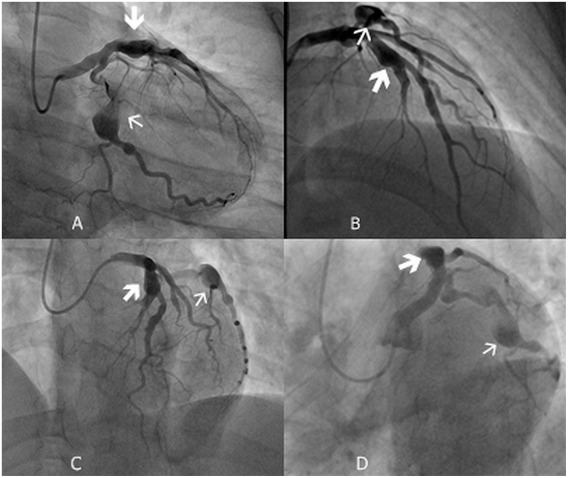

O infarto agudo do miocárdio é a causa mais comum de morte global, sendo responsável por 32% dos óbitos no…